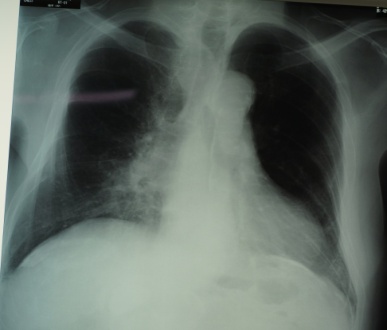

5. 建物ばく露

70歳男性、A医大で悪性胸膜中皮腫上皮型T1a.N0と診断された。職業歴は1949-1950年農業、1950-1966年製紙用金網製造会社織工、1966-1969年喫茶店経営。1969年-2003年私鉄駅高架下文具店店長。2階倉庫の吹き付け材には、クロシドライトが25%含。解剖肺内アスベスト繊維濃度19.0×106本/乾燥1g解剖のアスベスト繊維でクロシドライト11本、クリソタイル・アモサイト1本合計13本観察した11)【図5】【写真5】。

• 2階倉庫の吹付け材にはクロシドライトが25%

• 文具店2階の静穏時の濃度は1.13~4.2f/L

• 1階に荷物搬入時の濃度は14.0f/L

• 2階に荷物搬入時と清掃時の濃度は136.5f/L

• 文具店1階は0.34~1.13f/L

• 文具店外の大気中の濃度は定量下限値

厚生労働省:中皮腫や肺がんで業務上疾患として労働者災害補償保険(労災保険)または石綿救済法(時効労災)で認定された人を毎年12月公表。「吹付け石綿のある部屋・建物・倉庫等での作業(建設業以外)」による石綿関連疾患は、2013(平成25年度)年までの集計で累積105名12)。105名の内訳は、中皮腫71名(労災64名、時効労災7名)、肺がん26名、石綿肺3名、良性石綿胸水2名、びまん性胸膜肥厚3名。職種ではビル管理、食品、薬品、ボーリング、デパート、大学等多様な職種となっている。